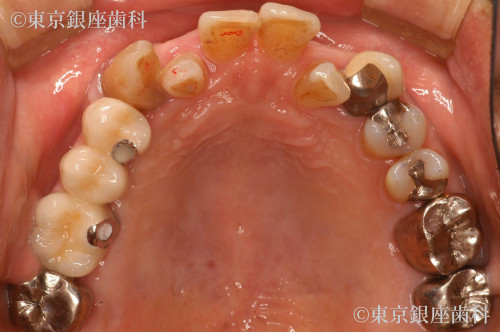

当院来院時にはインプラント除去した部位の粘膜も落ち着いていて義歯を使用できていた。

右上4番の動揺があり予知性が低いため同意を得て抜歯。サイナスリフトを併用した2本のインプラント埋入で右上456番の3本の補綴を行う事とした。